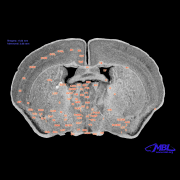

photomicrograph of

coronal section in

Macaca mulatta